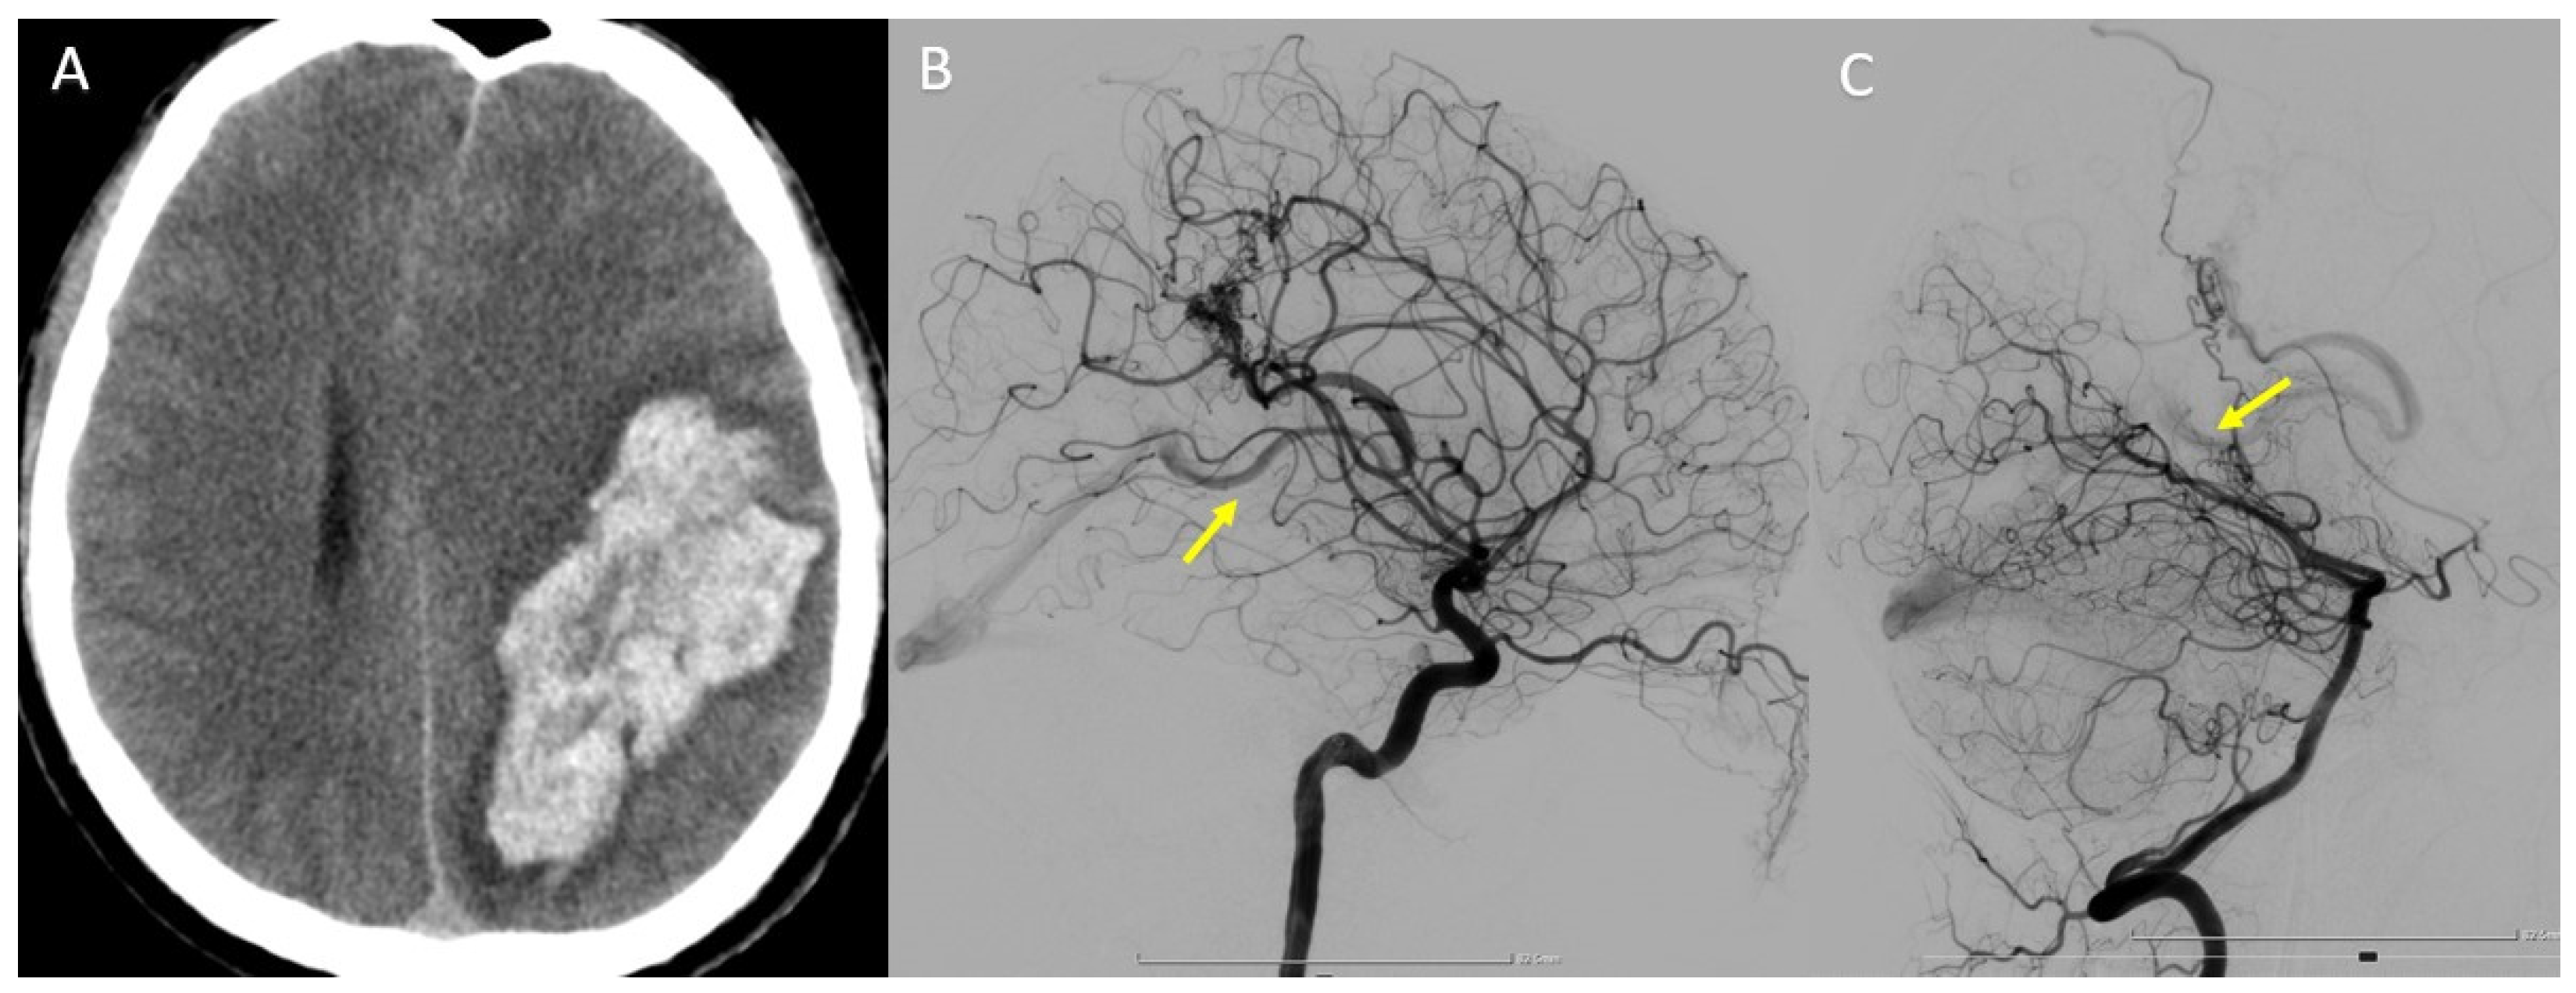

In this case, we present a 34-year-old patient who was diagnosed with temporoparietal parenchymal hemorrhage following a ruptured cerebral AVM (Figure 8A). DSA revealed that the nidus is supplied from two distinct vascular territories (Figure 8B,C).

Figure 8.

(A) Head CT scan—temporoparietal parenchymal hemorrhage. (B) Left internal carotid (ICA) DSA—lateral view. (C) Left vertebral artery (VA) DSA—lateral view. Yellow arrow—early filling of the deep venous system, and drainage to the great cerebral vein (of Galen).

In order to choose the best treatment strategy, a detailed analysis of the 3DRA images as well as the overlay between the two 3D volumes obtained by injecting both the left internal carotid artery and the left vertebral artery was required (Figure 9A–C). The analysis of the images showed that the arterial feeders originated from the left MCA and left PCA, while the deep venous drainage merges into the vein of Galen. The 3DRA imaging demonstrates the existence of multiple intranidal aneurysms, the largest being located near the feeder from the MCA.